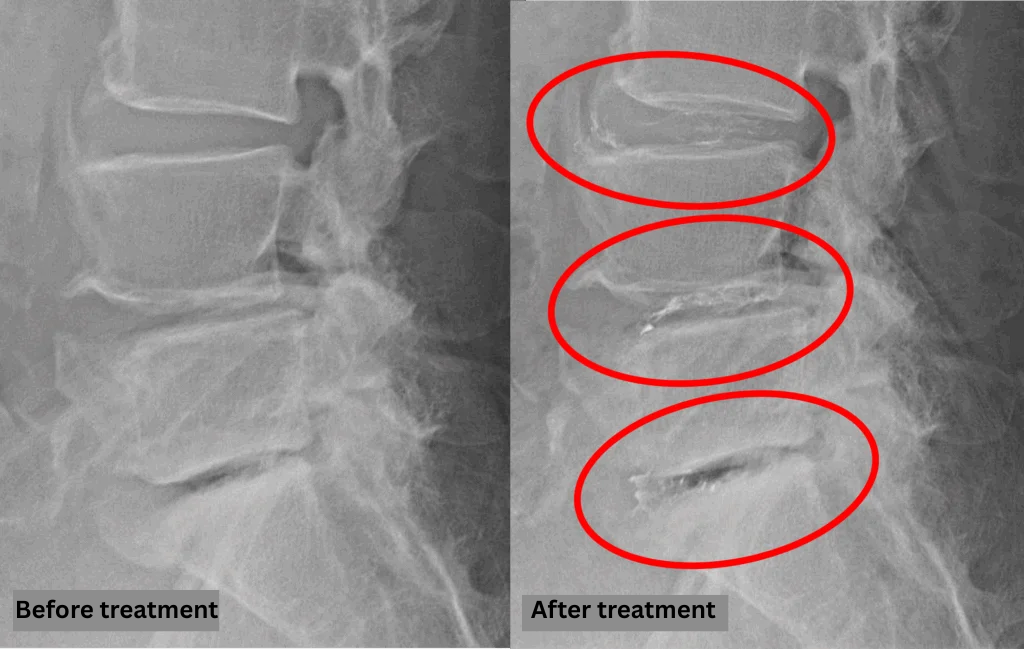

Imaging and findings

- L3/4: Disc degeneration, bulging

- L4/5: Disc degeneration, bulging, spinal canal stenosis

- L5/S: Disc degeneration, disc herniation

The above findings were also observed on the imaging.

These disc abnormalities at L3/4, L4/5, L5/S are highly likely to be the primary source of the patient’s symptoms due to compression of the spinal canal.